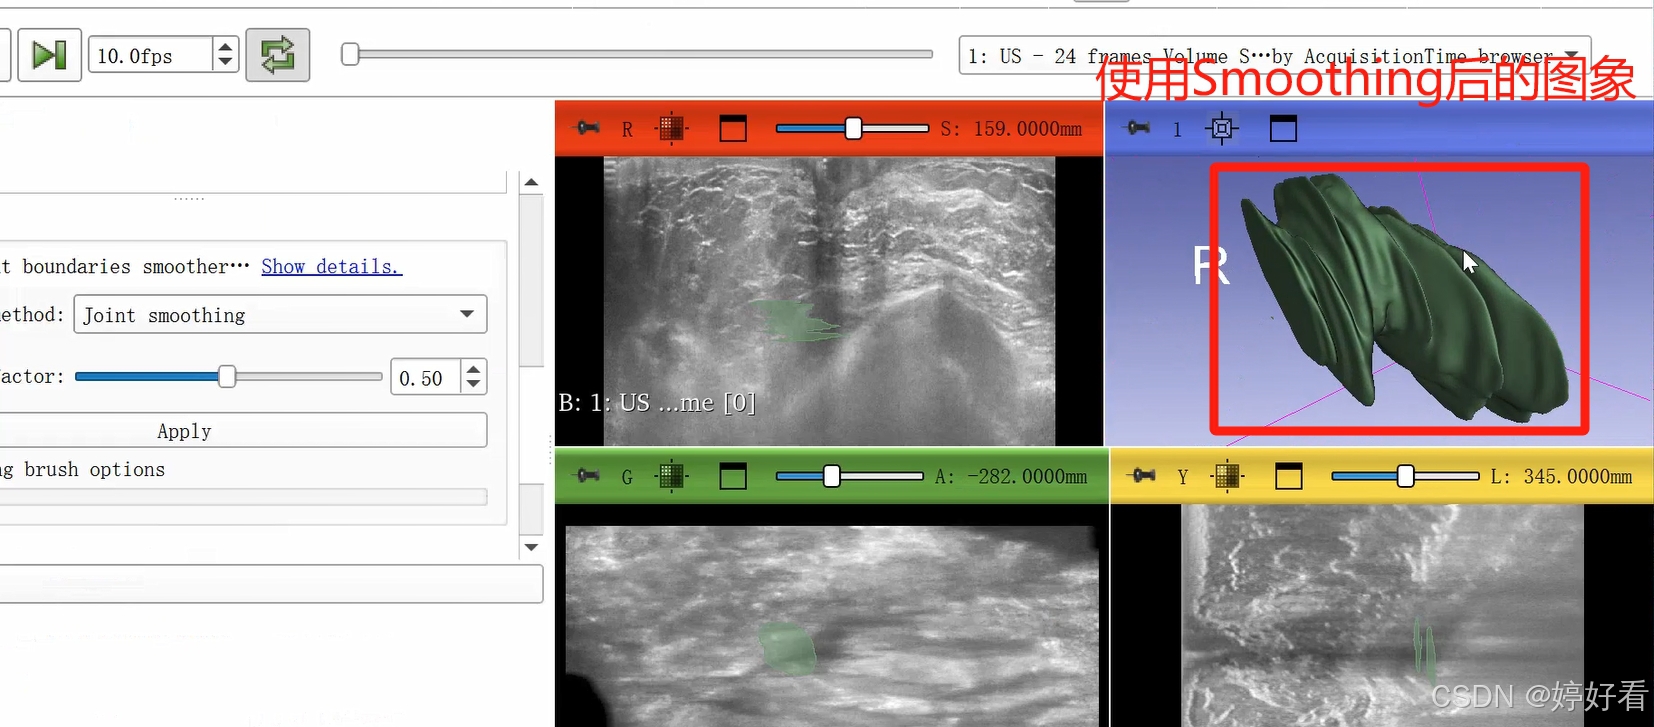

2.7 Smoothing功能使图像表面更光滑

首先,选中Smoothing功能,然后选择Joint smoothing,最后点击Apply。